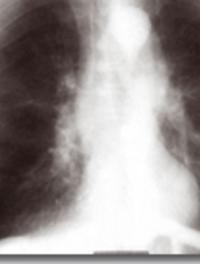

La fibrose pulmonaire idiopathique (FPI) est une maladie chronique d’évolution imprévisible au pronostic dramatique. Sa physiopathologie n’est pas encore totalement élucidée, toutefois le tabac joue probablement un rôle dans les agressions infracliniques répétées participant à la genèse de la maladie, tout comme les infections virales et bactériennes et la pollution. La présentation scanographique typique est celle d’une pneumopathie interstitielle commune (PIC) tout [...]